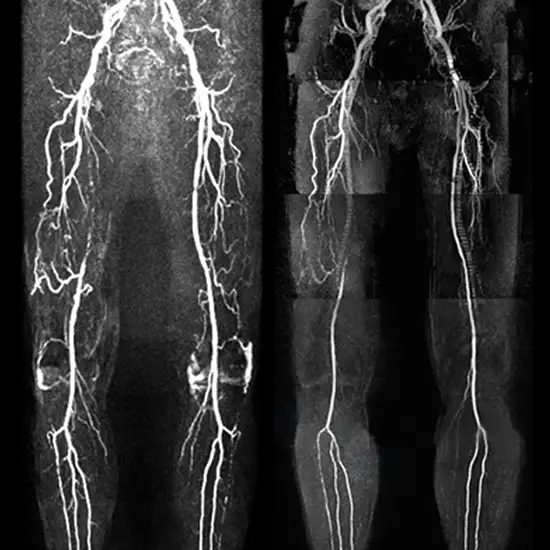

MR Angiography Left Lower Limb is an imaging tool of the lower limbs. It allows a thorough assessment of the arteries and veins in the left lower limbs. With the help of this procedure, The popliteal artery (subsequently separates into the tibial and fibular arteries) can be visualized. This procedure uses powerful magnetic waves and radio waves to obtain high-resolution 3D images. To perform this procedure, contrast media is given to the patients.